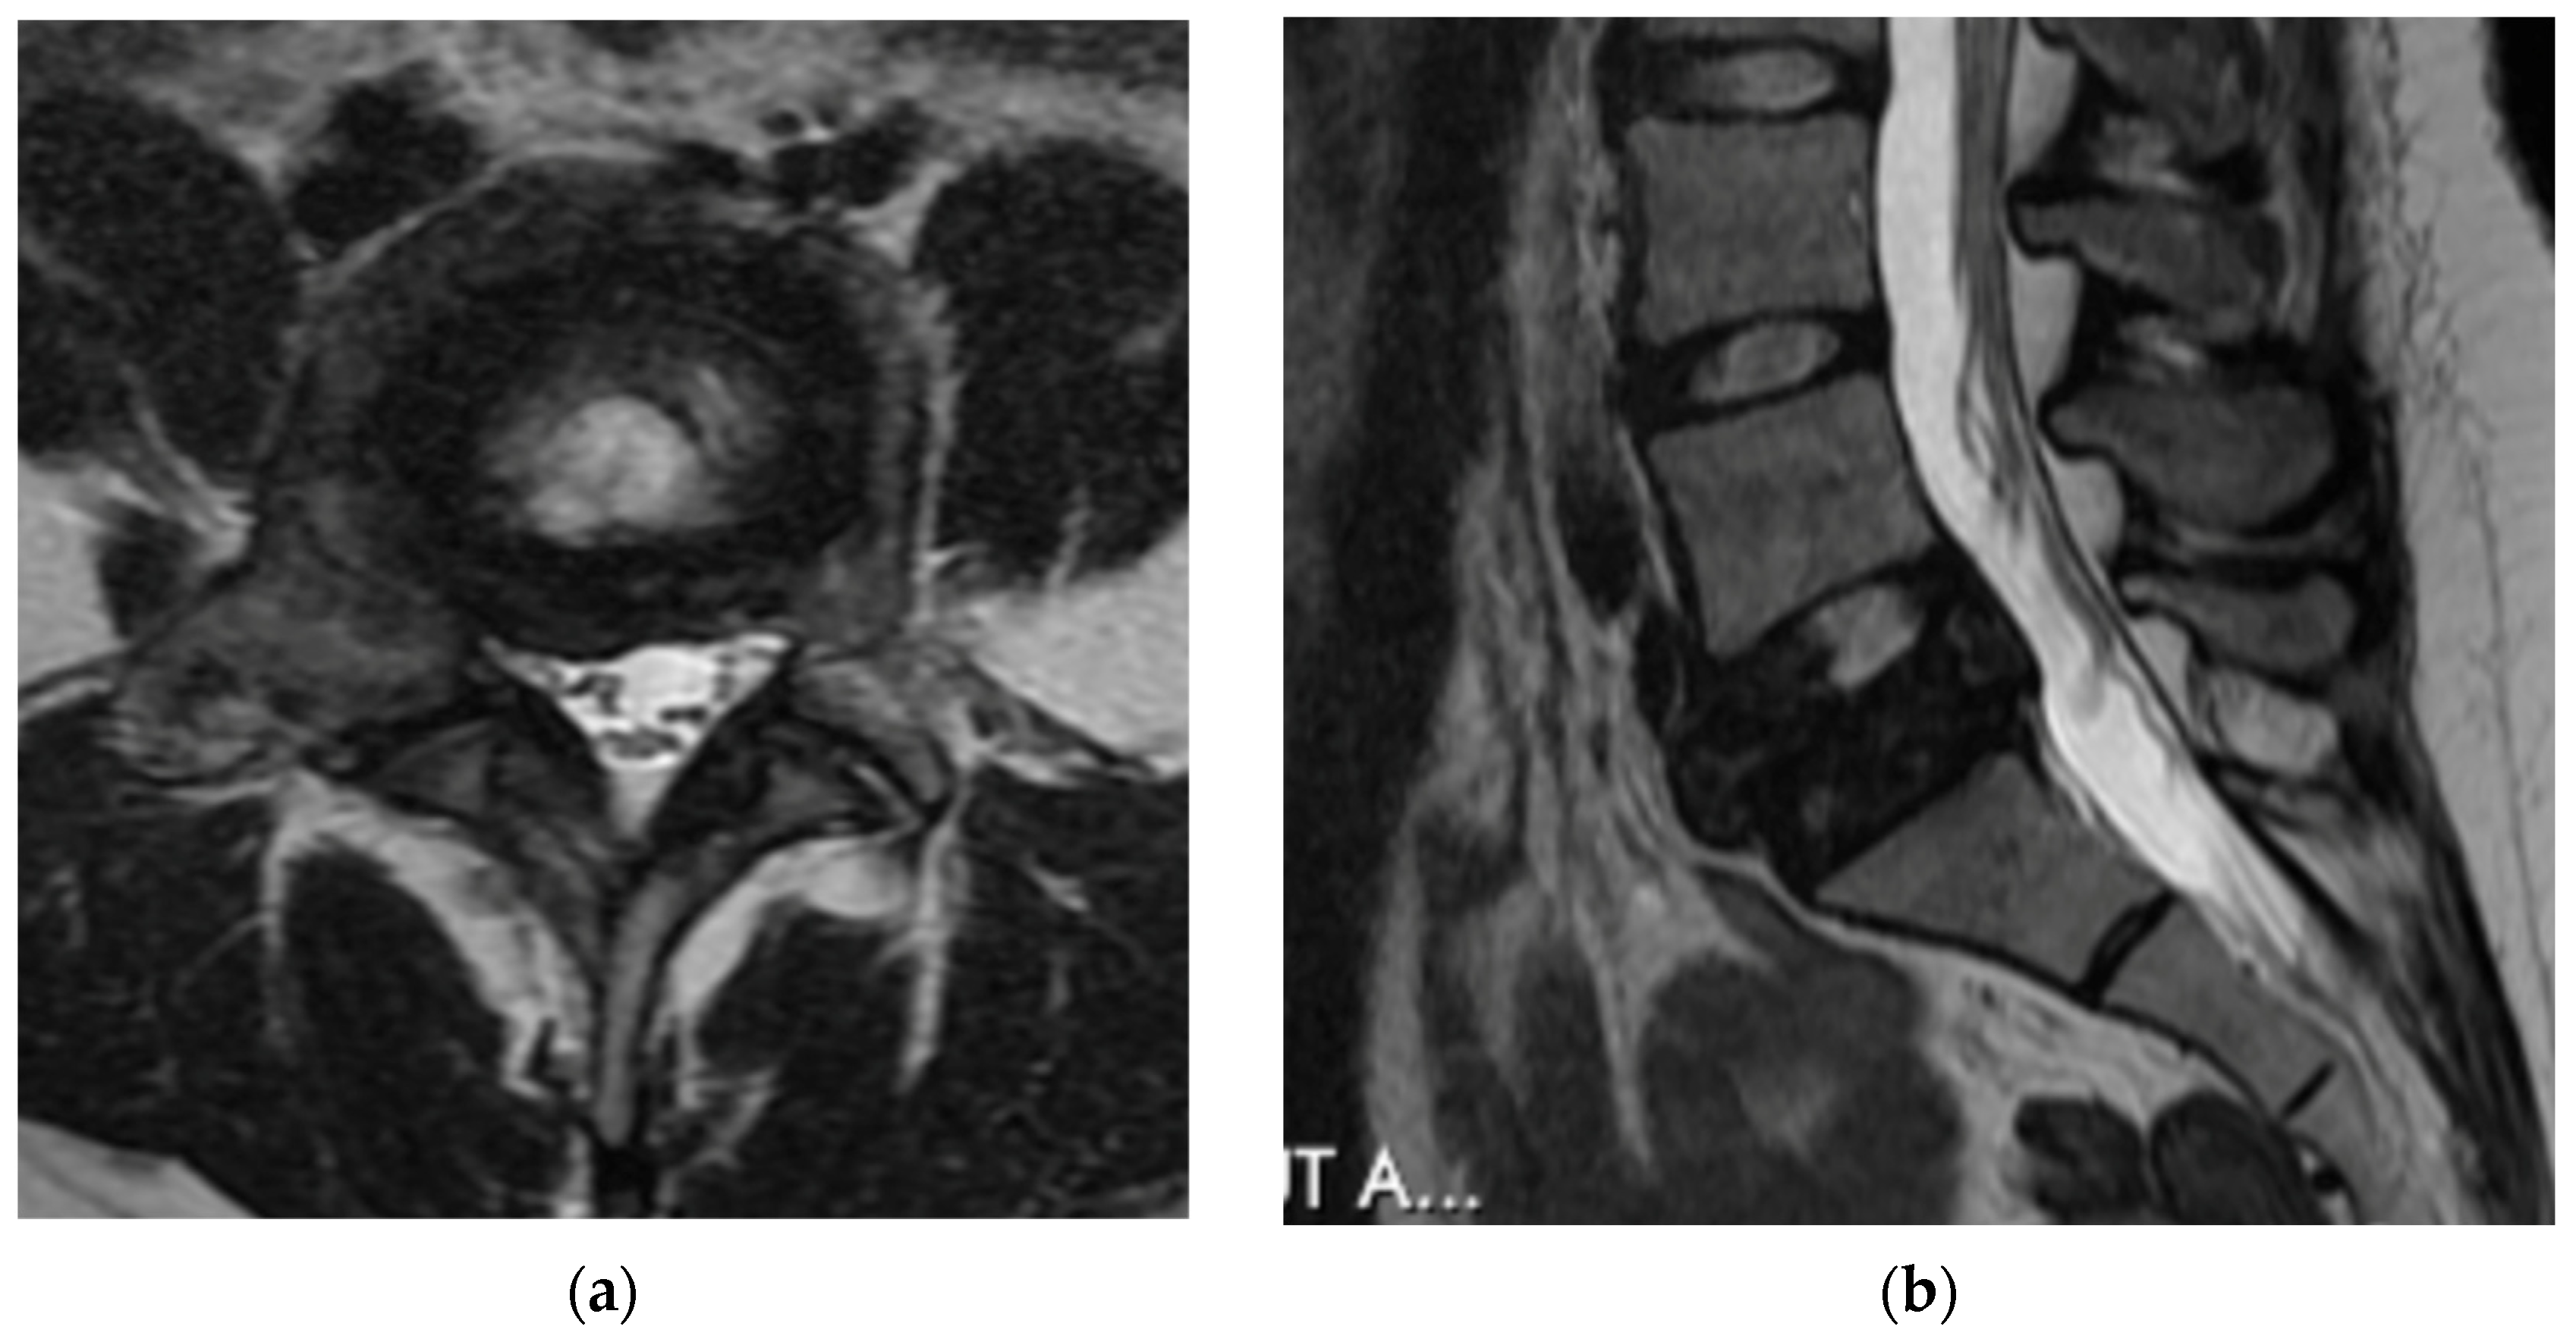

4.2.4. Computerized Tomography Scan